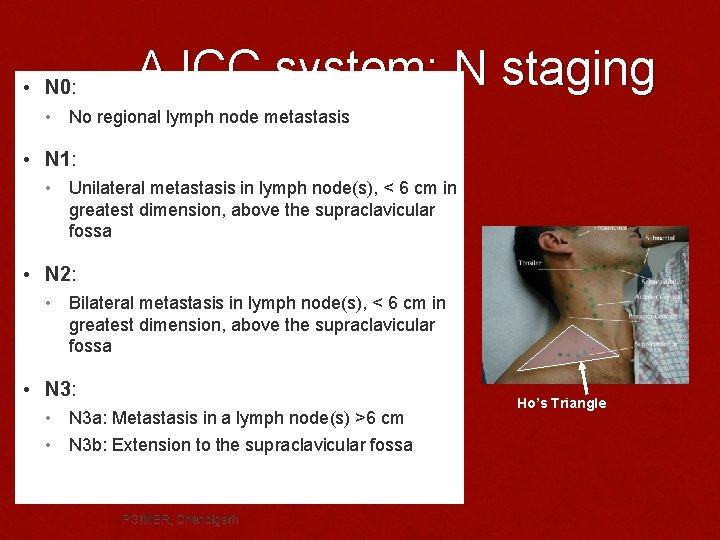

• N 0: AJCC system: N staging • No regional lymph node metastasis • N 1: • Unilateral metastasis in lymph node(s), < 6 cm in greatest dimension, above the supraclavicular fossa • N 2: • Bilateral metastasis in lymph node(s), < 6 cm in greatest dimension, above the supraclavicular fossa • N 3: • • N 3 a: Metastasis in a lymph node(s) >6 cm N 3 b: Extension to the supraclavicular fossa PGIMER, Chandigarh Ho’s Triangle